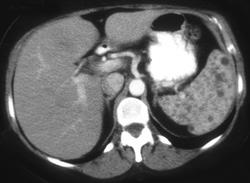

Splenic Lymphoma